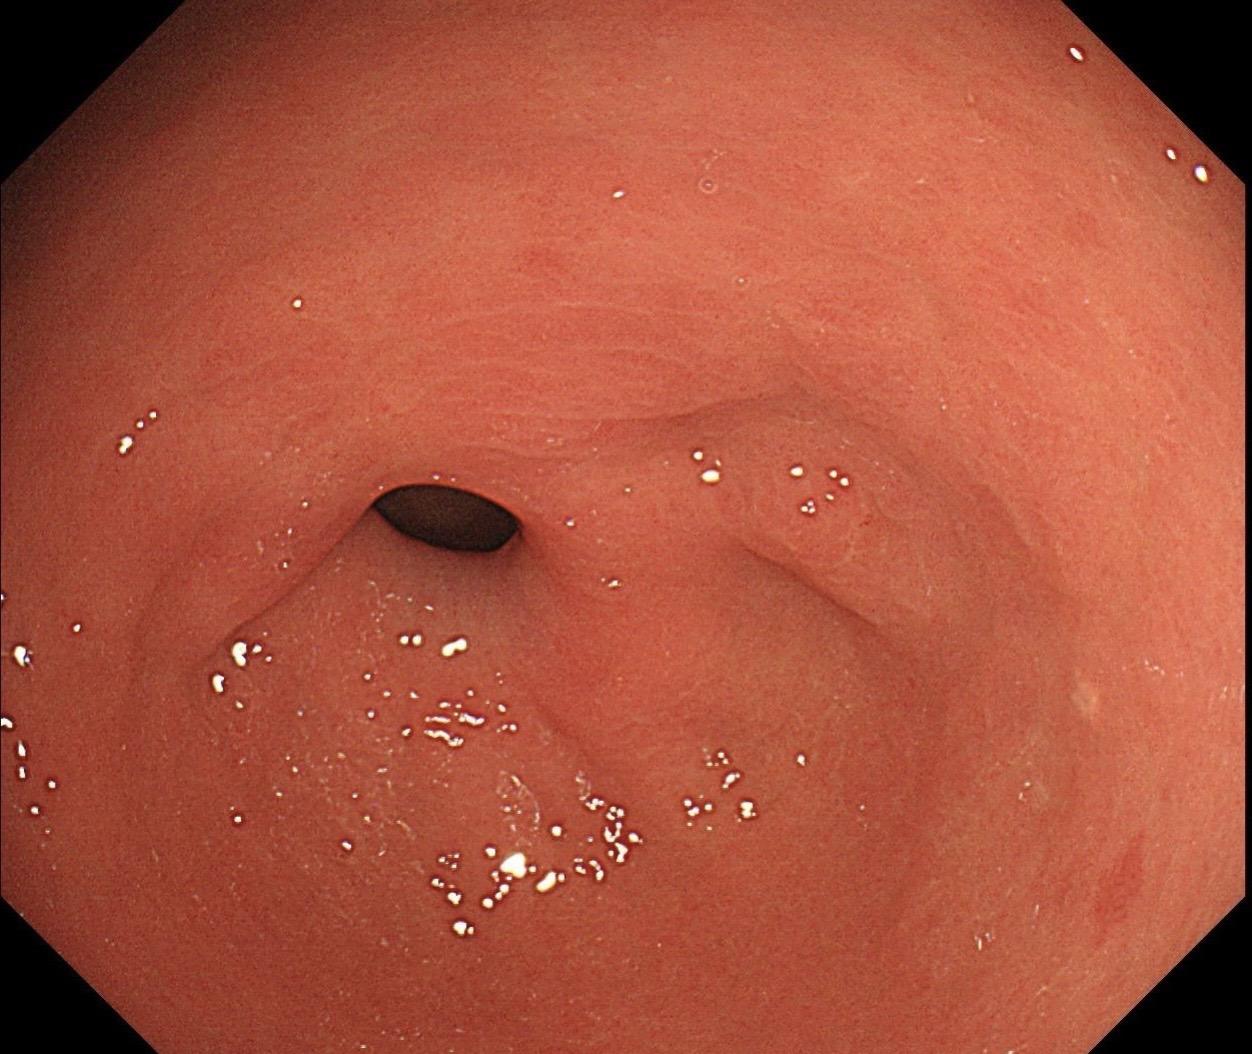

萎缩背景,注意那些微小的发黄色调。